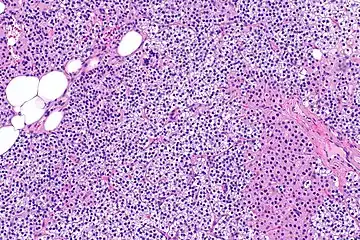

Parathyroid hyperplasia medium mag.

Primary hyperplasia of the parathyroid gland, results from both hypocalcaemia and increased phosphate levels by decreasing expression of calcium sensing receptors and vitamin D receptors at the parathyroid gland.[8][4] These decreases in receptor expression lead to hyperfunctioning of the parathyroid. Hyperfunction of the parathyroid gland is thought to exacerbate primary hyperplasia which evolves further to a secondary more aggressive hyperplasia. Histologically, these hyperplasic glands can be either diffuse or nodular.[24] Primary hyperplasia, usually resulting in diffuse polyclonal growth is manly related to reversible secondary hyperparathyroidism. Secondary hyperplasia of the parathyroid gland is more often a nodular, monoclonal growth that sustains secondary hyperparathyroidism and is the catalyst in the progression to tertiary hyperparathyroidism. Nodular hyperplastic glands in tertiary hyperparathyroidism are distinctly larger in both absolute size and weight up to 20-40-fold increases have been reported.[25][26][24]

Parathyroid glands are normally composed of chief cells, adipocytes and scattered oxyphil cells.[27][14] Chief cells are thought to be responsible for the production, storage and secretion of parathyroid hormone. These cells appear light and dark with a prominent Golgi body and endoplasmic reticulum. In electron micrographs, secretory vesicles can be seen in and around the Golgi and at the cell membrane. These cells also contain prominent cytoplasmic adipose.[27][14] Upon onset of hyperplasia these cells are described as having a nodular pattern with enlargement of protein synthesis machinery such as the endoplasmic reticulum and Golgi. Increased secretory vesicles are seen and decreased intercellular fat is characteristic.[27][24] Oxyphil cells also appear hyperplasic however, these cells are much less prominent.